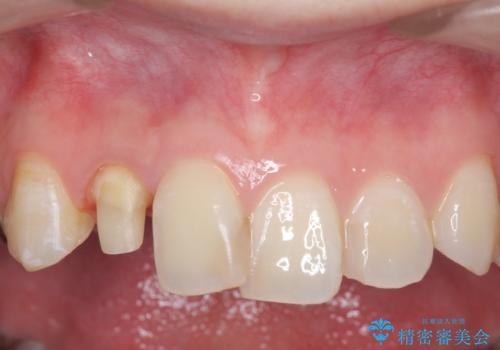

- 右上2番目の歯の被せ物と歯茎の間の継ぎ目が気になるといらっしゃった方の症例です。

再根管治療は希望されなかったため、クラウン除去後、オールセラミッククラウン(スペシャル)による補綴を行いました。